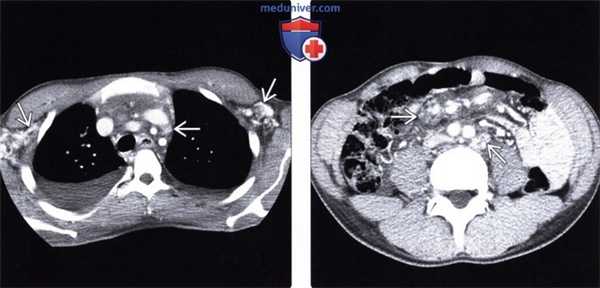

(Слева) При аксиальной КТ с контрастным усилением у пациента со СПИДом и диссеминированной саркомой Капоши (СК) определяется распространенная внутритрудная лимфаденопатия. Многие из лимфатических узлов гиперваскулярны, что характерно для СК.

(Справа) На аксиальной КТ с контрастом у этого же пациента определяется выраженная внутрибрюшная лимфаденопатия с усилением лимфоузлов при контрастировании, что помогает отличить СК от лимфомы или других причин лимфаденопатии.